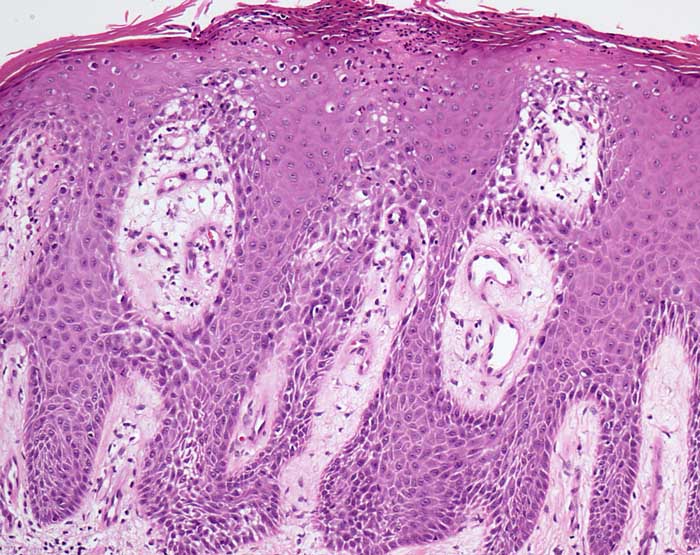

PathoPic – image database / PathoPic ID 6834 - Psoriasis vulgaris

Psoriasis vulgaris

Regelmässige Akanthose und stark elongierte gleichlange Reteleisten. Die Reteleisten sind teils dünn, teils am unteren Ende kolbenförmig verbreitert. ${qy8032822Parakeratose mit Neutrophilen} Fokale Parakeratose mit Ansammlungen von neutrophilen Granulozyten. Das $o{ab15759sehr dünnes Str. granulosum} Stratum granulosum fehlt weitgehend. Leichte Spongiose (interzelluläres Ödem) der unteren Epidermisabschnitte. Ödematöse Papillen mit gewundenen ektatischen Kapillarknäueln reichen bis nah an die Hautoberfläche heran. Perivsakuläres lymphozytäres Infiltrat.

Die Histomorphologie ist stadienabhängig. Das Bild zeigt eine vollentwickelte Läsion.